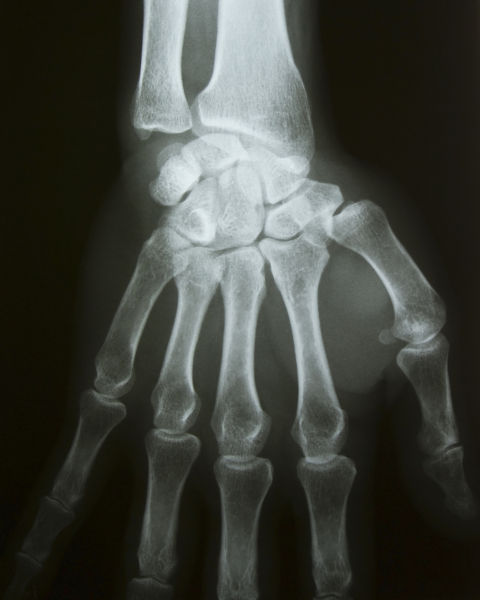

→ Raios X

Os raios X correspondem à faixa dos 0,01nm - 10nm do espectro eletromagnético. Esse é o segundo tipo de onda mais energético de todo o espectro eletromagnético. As máquinas de radiografia são capazes de produzir esse tipo de onda eletromagnética e são largamente usadas na medicina para analisar fraturas internas de forma não invasiva, já que esse tipo de radiação ionizante tem uma boa capacidade de penetração.

Radiografia de uma mão em texto sobre espectro eletromagnético.

Os raios X usados em radiografias permitem que profissionais da saúde visualizem os ossos sem precisar realizar uma incisão.